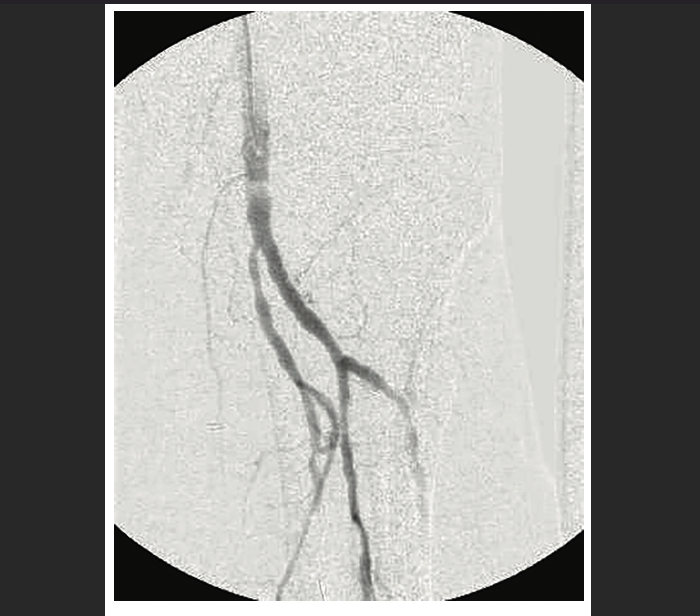

TCTAP C180 Reverse CART Technique in Above Knee Peripheral CTO Cart And Reverse Cart Technique Stent reverse cart entails creation of an open target for retrograde guidewire navigation when a stent is. The “stent reverse cart” technique involves deploying a stent within the antegrade dissected plane to create an open target for retrograde crossing. Controlled antegrade and retrograde subintimal tracking (cart) and reverse cart. Two rdr techniques are available: The most commonly used retrograde crossing. Cart And Reverse Cart Technique.